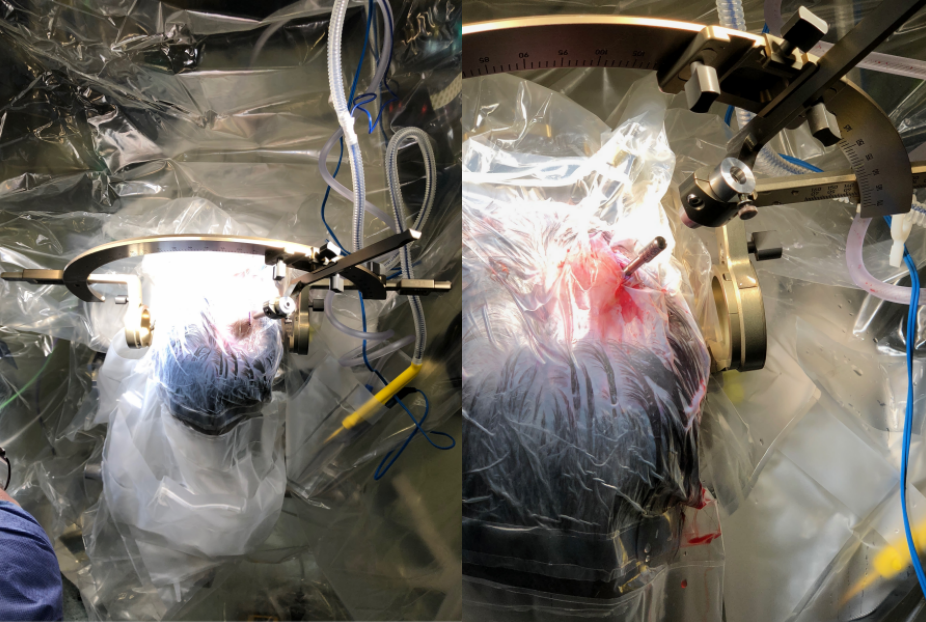

再按照手术方案设定手术入路轨迹后,插入激光探针准备消融

Rutka教授和他的团队正在为其手术